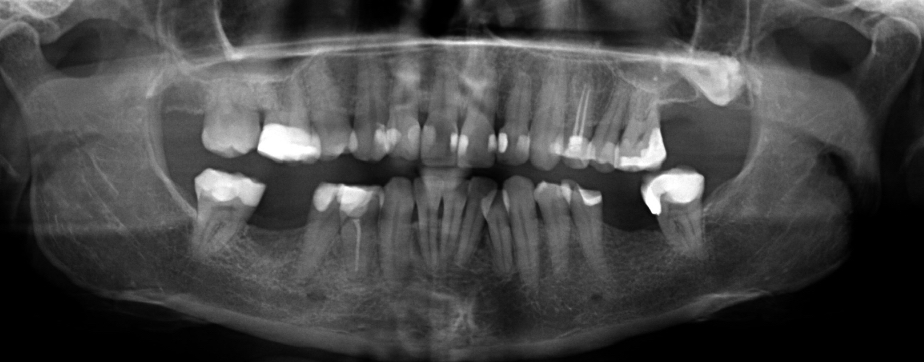

Zie de bijgevoegde foto. Mijn tandarts vond implantaten beter dan een brug voor mij. Denkt u ook op basis van de foto dat er voldoende bot is rechts?

Voor de aansluiting op het buur element vind ik niet dat daar ook een kroon nodig is...wel ivm de grootte v d vulling. Ik zie meerdere grote vullingen zo ook kiezen met wkb behandeling.

Op de opt zie ik:

- Bot afbraak (hoop niet dat u rookt of heeft gerookt._.

- De 28 is aanwezig, zou ik laten zitten als u er geen last v heeft.

- Zou de wortelpunt v d 24 extra controleren met een x-foto.Eventueel indien nodig dan een herbehandeling voordat er een kroon op gemaakt zou worden, als u kiest voor een vaste voorziening, uitneembaar (frame) is goedkoper.

- Er zijn meerdere grote vullingen waar ik een kroon op zou overwegen. 24/25/26/37/35/44/45/47/16 (niet echt goed te beoordelen maar ga uit v de geleverde foto.). Kronen op de voortanden lijken vooralsnog nog niet nodig maar hangt ook v h esthetische af.

-Nogmaals meerdere kronen zijn niet nodig als u uitgaat v e uitneembare voorziening bijv. een frame prothese.

Botafbraak kan nog v toen u nog rookte zijn,,,,dan zou ik uw foto bibliotheek moeten beoordelen. bovenkaak met name 17/26 en de 37/47.